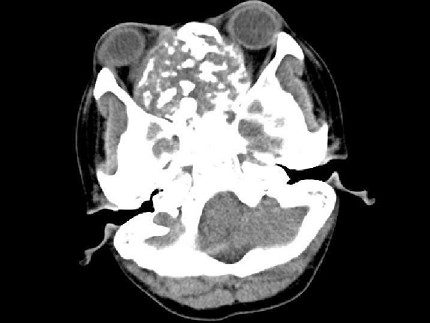

[多选题]男性,28岁,因鼻塞、头痛1年余,鼻窦CT扫描如图所示,请选择正确的描述与结论()A.双侧上颌窦、筛窦、鼻腔及蝶窦内见软组织肿块影B.肿块内密度不均,

A.双侧上颌窦、筛窦、鼻腔及蝶窦内见软组织肿块影

B.肿块内密度不均,有较多致密钙化影

C.窦壁及颅底骨质破坏